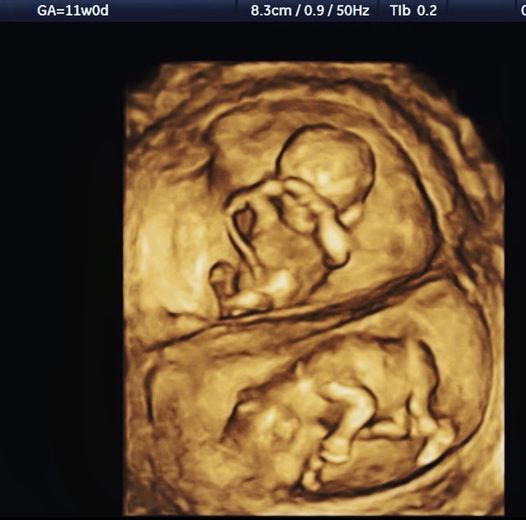

關於臍帶 關於臍帶 星期六 莫名的 就想po這張 喔喔對了 請各位同學不要再問我臍帶是什麼時候才會長出來的 你看到了 臍帶是一開始就會在 不可能是之後長出來然後再接上去的 就醬 FB原文討論串 分享此文: 分享到 X(在新視窗中開啟) X 分享到 Facebook(在新視窗中開啟) Facebook 喜歡 正在載入... 相關 發表留言 取消回覆 Δ